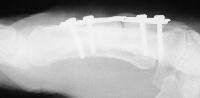

He did well for three months, then broke his plate:

The plate was removed, and the fracture was replated, using more bone graft and larger screws. This plate  held for five months, then also broke. Additionally, a cross union to the ring metacarpal can be seen: